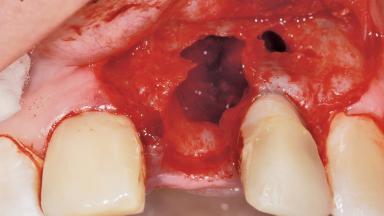

A 36-year-old female patient was referred for the replacement of the upper left central incisor (tooth 21), which had fractured. Although the tooth had been asymptomatic for many years, the crown began to loosen, at which time she presented to her dentist for an assessment. Teeth 21 and 22 had both been endodontically treated many years previously. She was a healthy individual and a non-smoker.

Bone Volume | Deficient horizontally, requiring prior grafting |